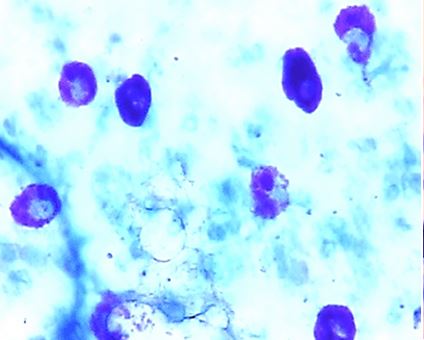

Подсчет тучных клеток производится минимум в пяти гистологических срезах одного органа, окрашенных толуидиновым синим по А. Унна, после чего полученные данные вводятся последовательно с каждого среза, полученные для данного органа индексы усредняются.

Тучные клетки с разной степень дегрануляции и сульфатирования в:

А) капсуле почки

Б) тимусе крысы линии Вистар. Окраска по Унна. 40×